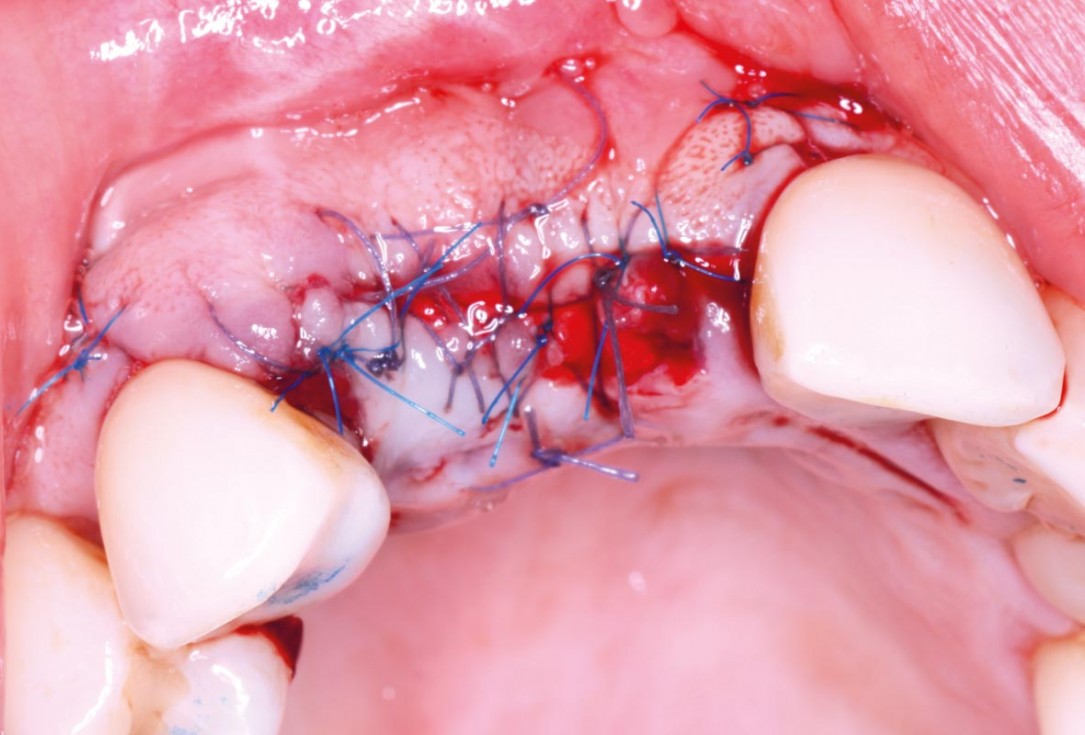

07/10 - Interrupted sutures with 5-0 resorbable sutures on the crest and 6-0 non-resorbable sutures for the releasing incisionsMaxillary bone reconstruction in the anterior area with cerabone® and Jason® membrane - Dr. P.-Y. Gegout & Prof. O. Huck